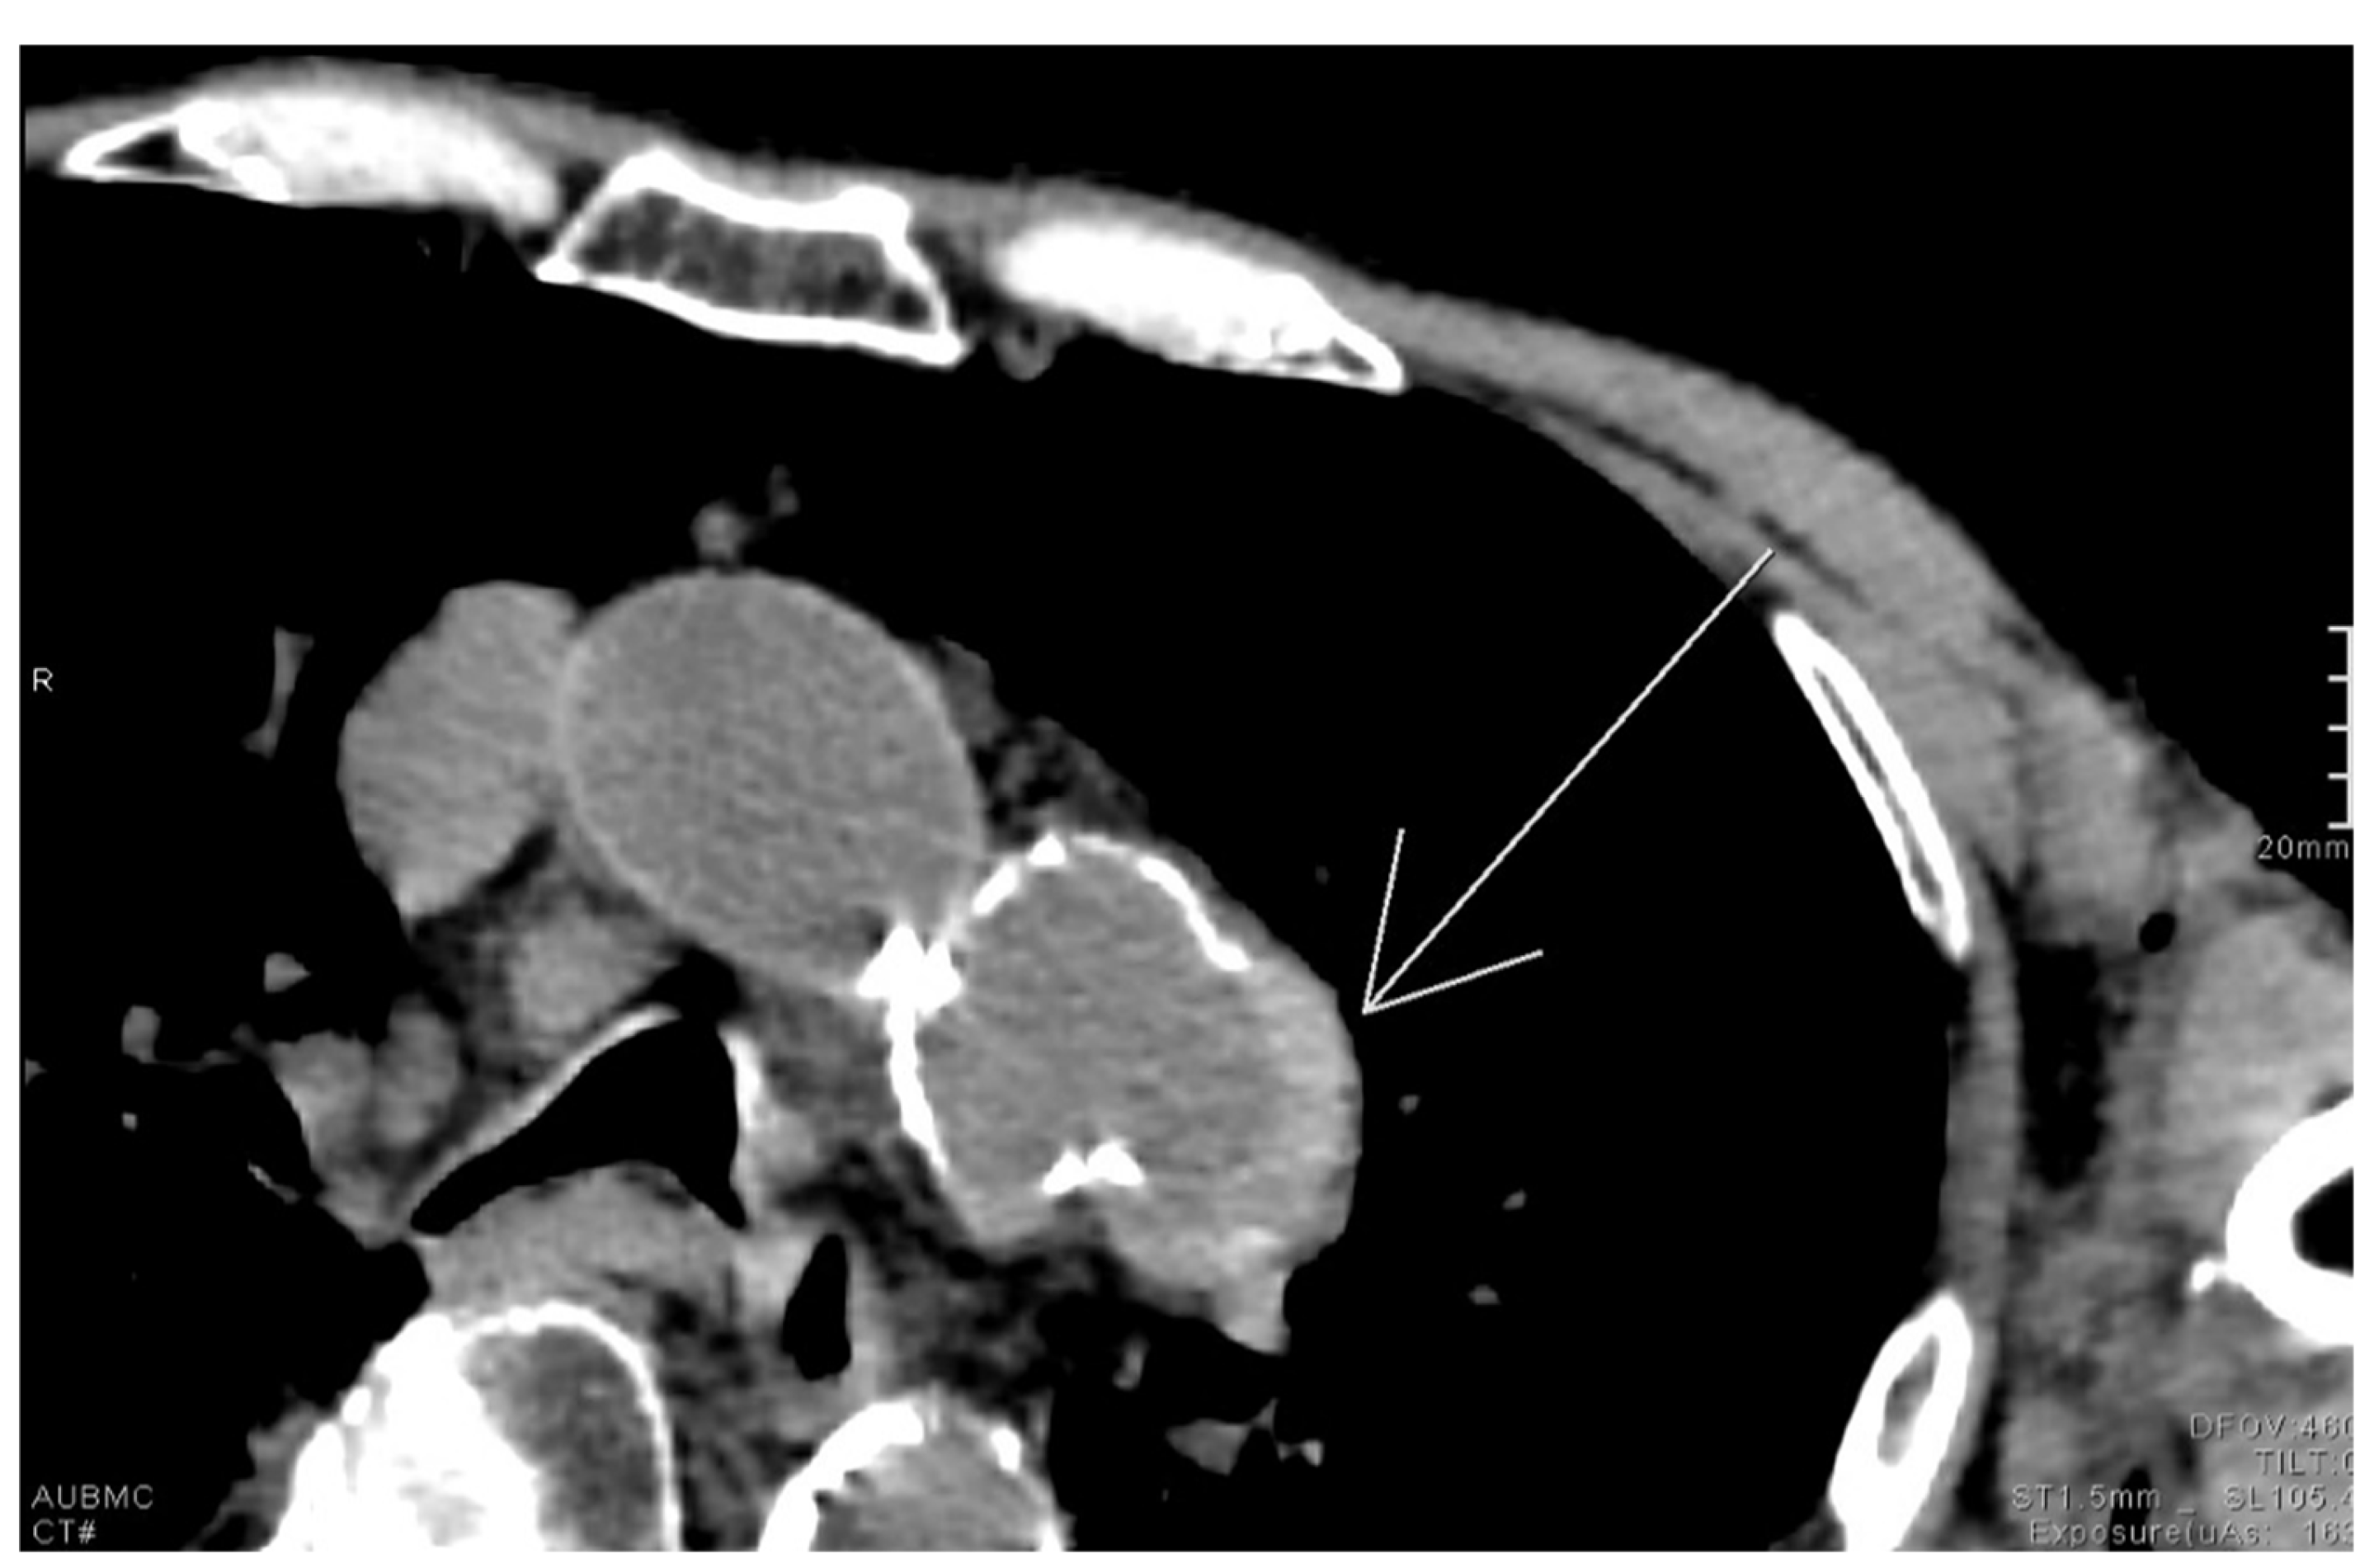

2.14. Air Crescent Sign

- Burkhardt, J.; Arshanskiy, Y.; Munson, J.; Scholz, F. Diagnosis of Inguinal Region Hernias with Axial CT: The Lateral Crescent Sign and Other Key Findings. Radiographics 2011, 31, E1–E12. [Google Scholar] [CrossRef]

- Hasbahceci, M.; Erol, C. Usefulness of Computed Tomography for Differentiation of Primary Inguinal Hernia. Gazi Med. J. 2015, 26, 170–173. [Google Scholar]